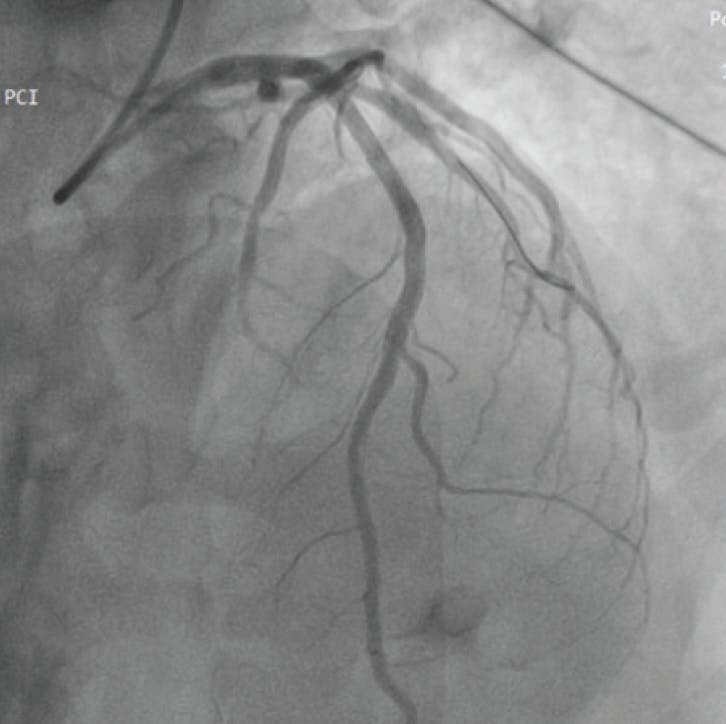

Three CAT RX passes were performed from proximal to distal, with aspiration continuously on as the catheter was advanced in a slow, controlled manner. Angiography after CAT RX showed an optimal thrombus resolution and lesion visualization. A stent was then placed, resulting in final TIMI III flow with preservation of all side branches (Figure 3). At the end of the procedure, we retrieved a massive 3.5-cm-long thrombus from the Penumbra canister (Figure 4).

Figure 3. Angiographic view (cranial 40°) showing final TIMI III flow after CAT-RX and stenting in the LAD.